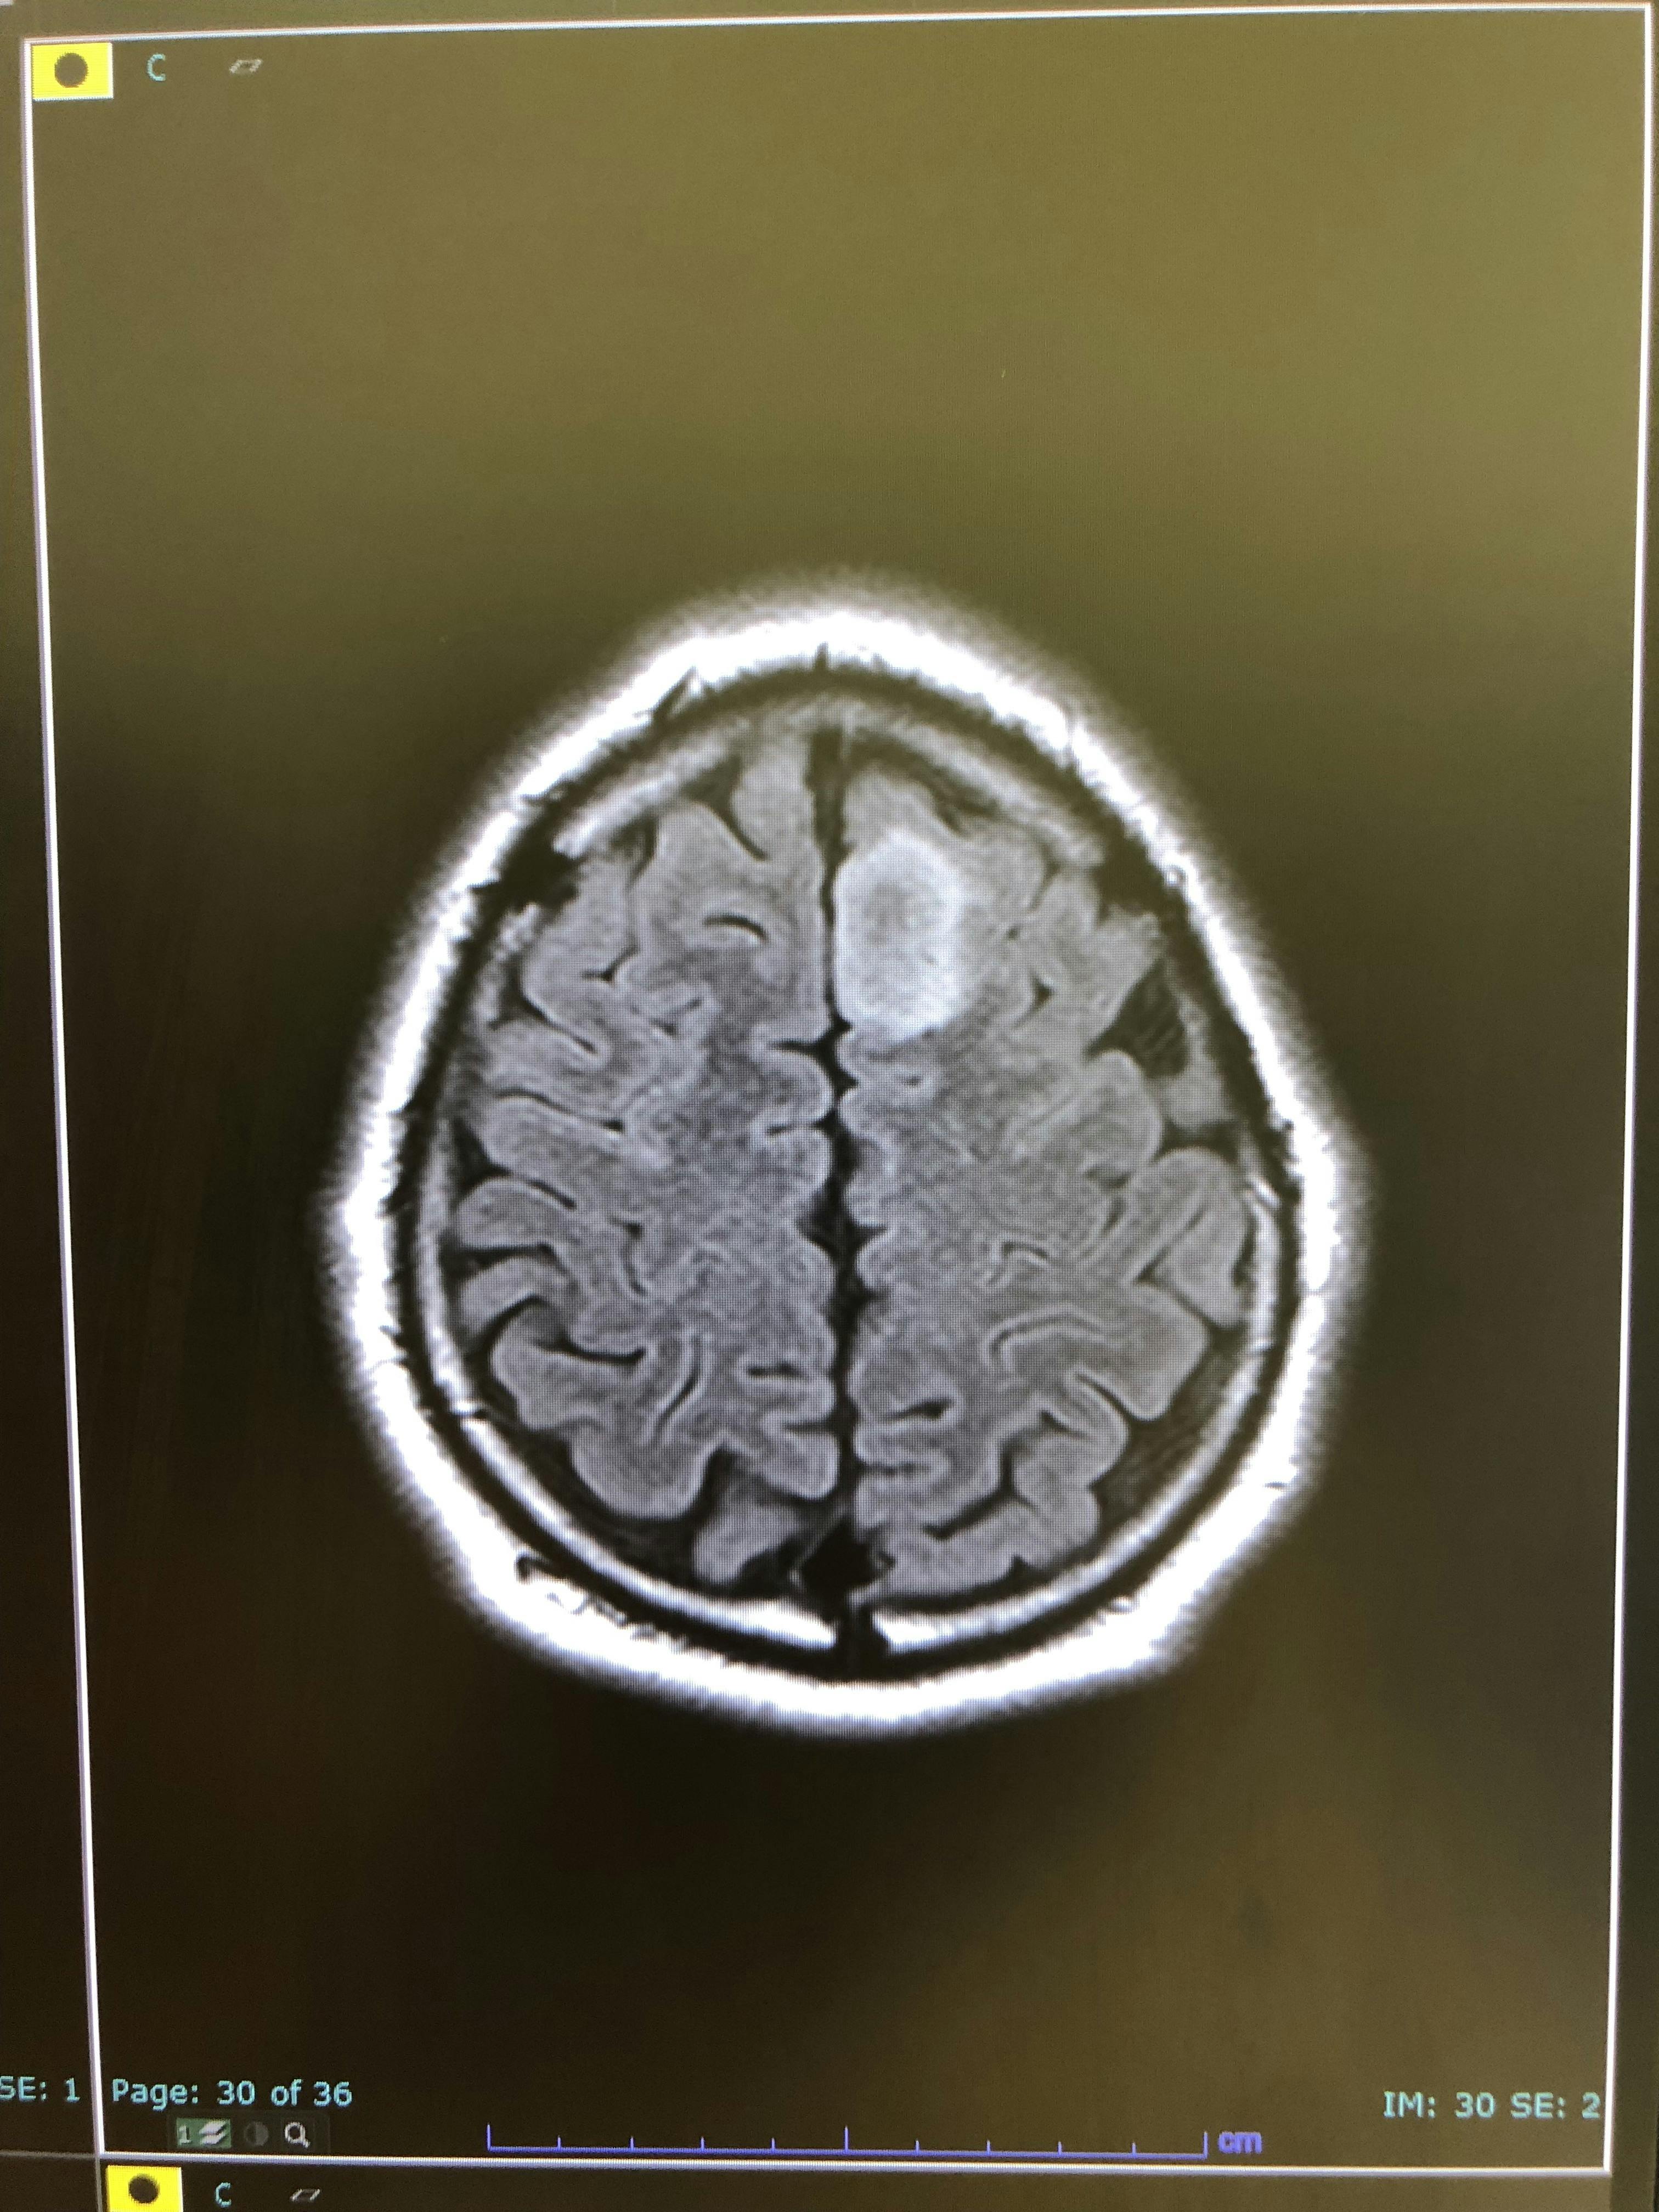

すぐに近くの病院へ行き、MRIを撮ると…

素人目でも「ん?なにかあるな?」と分かりますよね…